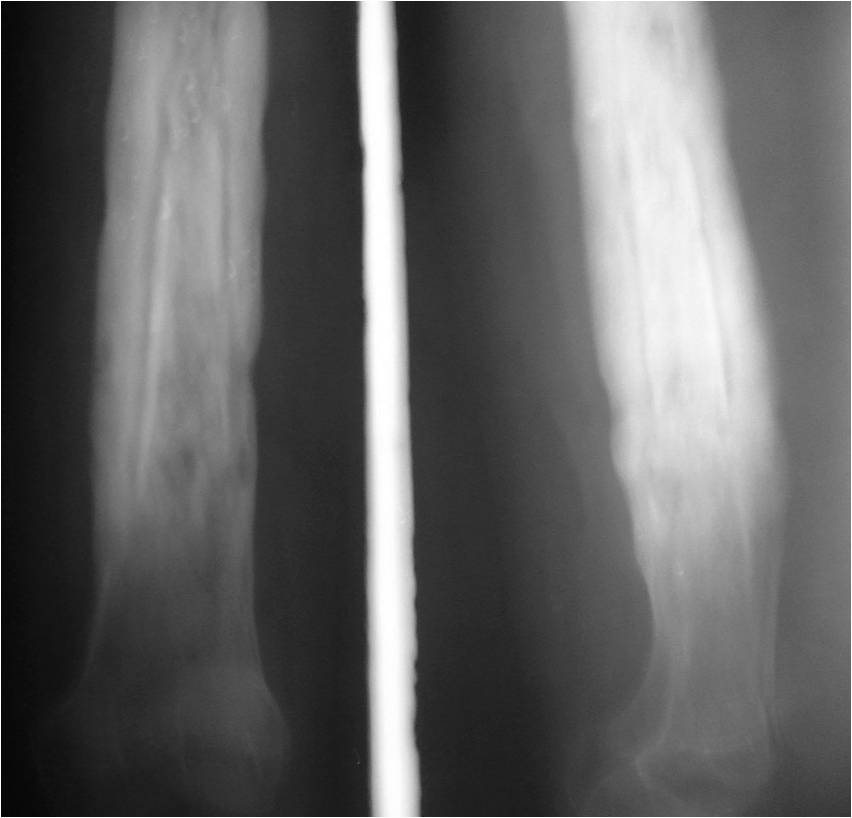

Radiograph shows physiological periosteal reaction in the left ulna of Periosteal Reaction X Ray a periosteal reaction is the formation of new bone in response to injury or other stimuli of the periosteum surrounding the bone. the periosteum is a membrane several cell layers thick that covers almost all of every bone. learn about the different types and causes of periosteal reaction, a membrane that covers the majority of. periosteal. Periosteal Reaction X Ray.